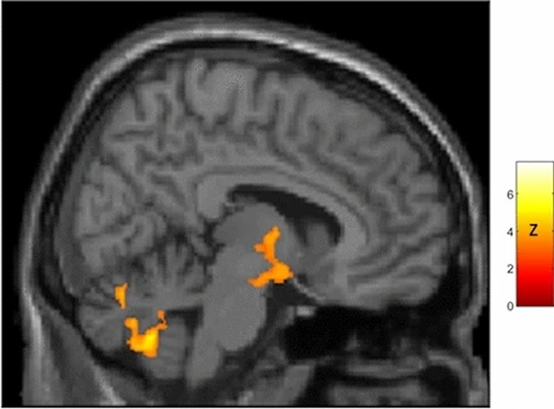

全腦統計z圖的矢狀視圖(中線右側;X=8),顯示了女性大腦年齡相關TSPO表達高于男性的區域,在跨越下丘腦和丘腦的區域中有顯著的結果(下丘腦峰值:X=11,Y=-7,Z=-13[Z=4.2];丘腦峰值:X=4,Y=-6,Z=0[Z=5.1];下丘腦重心:X=10,Y=-5,Z=-9。這種性別差異對應于下丘腦中顯著的年齡相關TSPO表達:X=0,Y=-,Z=-9。這種性別差異對應于女性下丘腦中顯著的年齡相關TSPO表達(峰值:X=8,Y=0,Z=-12[t=3.3;p-校正=0.002]),而不是男性。與女性相比,男性沒有更大的與年齡相關的TSPO表達區域。圖片由科學報告提供。